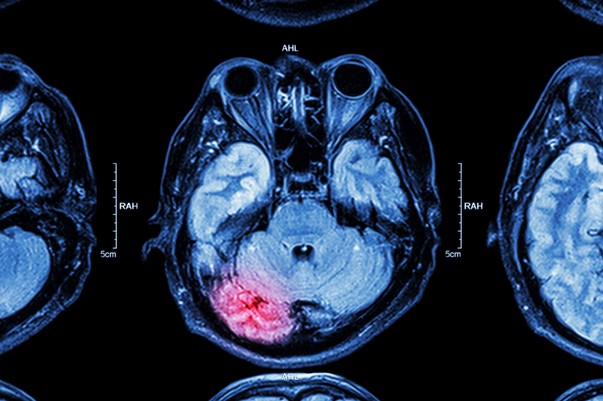

MRI of brain : brain injury

Après la maladie d’Alzheimer, la maladie de Parkinson est la deuxième maladie neuro-dégénérative la plus fréquente. Outre les facteurs génétiques, cette pathologie peut également se développer en raison de facteurs environnementaux. Parmi eux, de nombreuses études ont démontré un lien entre la survenue de la maladie de Parkinson et une exposition aux pesticides, notamment chez les agriculteurs. Mais aucun produit précis n’a été jusqu’ici mis en cause.